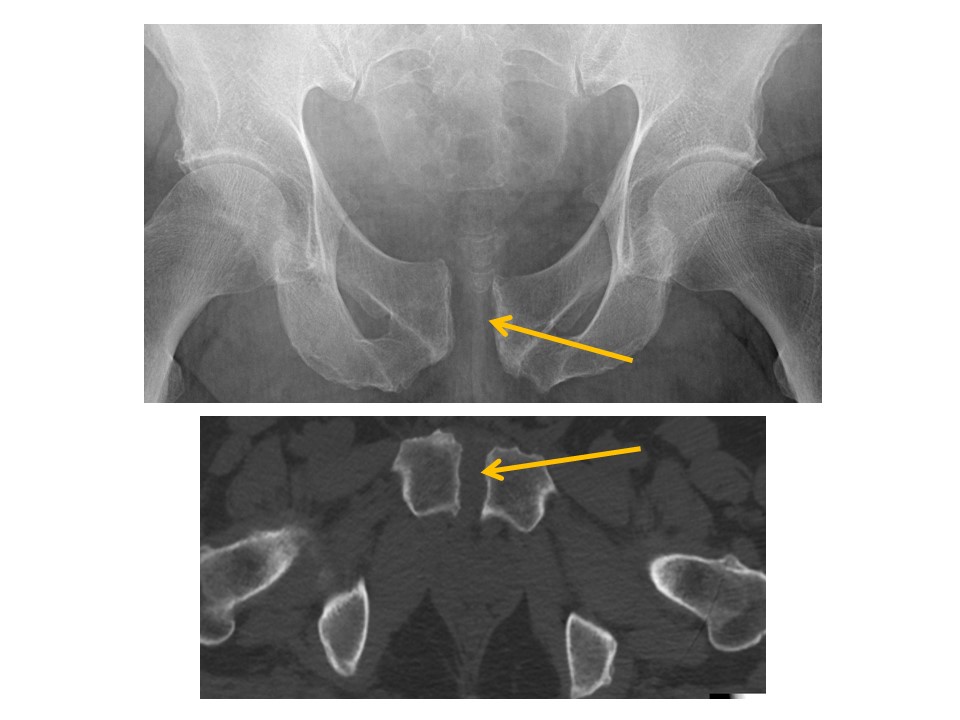

PUBIC SYMPHYSIS and RAMI

There is a pubic ramus fracture. [Yes/No]

There are avulsion fractures at the ischial tuberosities. [Yes/No]

ILIAC BONES

Iliac wing fractures are present. [Yes/No]

Posterior iliac bone fractures are present. [Yes/No]